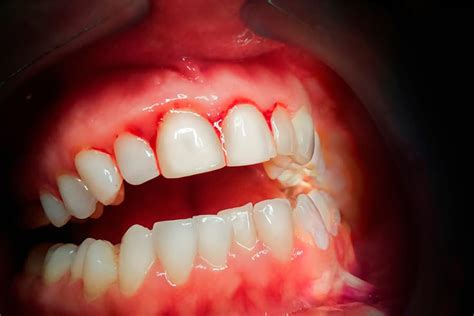

No es normal que sangren las encías al cepillarse los dientes. Precisamente, el sangrado de las encías es uno de los síntomas de la enfermedad periodontal. El sangrado de las encías es un signo evidente de que algo no funciona bien. Por ello se recomienda acudir al especialista una vez que se produzca esta situación.

Si sale sangre de las encías, suele deberse a gingivitis. Las encías están rojas, hinchadas y sensibles a la presión. Especialmente por la mañana o por la noche, al cepillarse los dientes o al utilizar el hilo dental, puede empezar a sangrar rápidamente en la zona inflamada. Esto se debe a que el cuerpo bombea automáticamente más sangre a las encías cuando se produce una inflamación, para poder eliminar más rápidamente las bacterias responsables de la inflamación. El sangrado de las encías suele producirse en un solo lugar, por ejemplo, en un diente molar o también en un implante.

La superficie rugosa del sarro es un verdadero paraíso para las bacterias, que pueden seguir propagándose por aquí. El problema: segregan sustancias tóxicas que atacan las encías y provocan inflamación. El cuerpo reacciona bombeando más sangre al lugar del ataque para eliminar las bacterias. Gingivitis es el término técnico para la inflamación de las encías. Además del sangrado de las encías, la inflamación y el enrojecimiento de las encías también indican una gingivitis aguda. Con una higiene bucal exhaustiva, la gingivitis -y por tanto el sangrado de encías- suele desaparecer al cabo de una o dos semanas. Por regla general, no causa dolor.